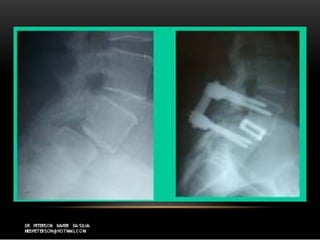

TraumáticaTraumática

 Fratura de elementos posterioresFratura de elementos posteriores

 Espondilolise traumáticaEspondilolise traumática

 Movimento de hiperextensãoMovimento de hiperextensão

 Listese ocorre meses ou anos após o traumaListese ocorre meses ou anos após o trauma

 ““Espondilolistese istimica”Espondilolistese istimica”

TraumáticaTraumática  Fratura deelementos posterioresFratura de elementos posteriores  Espondilolise traumáticaEspondilolise traumática  Movimento de hiperextensãoMovimento de hiperextensão  Listese ocorre meses ou anos após o traumaListese ocorre meses ou anos após o trauma  ““Espondilolistese istimica”Espondilolistese istimica”